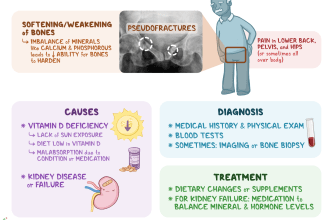

Rickets is a childhood disease that is primarily caused